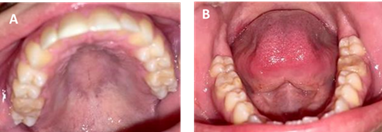

A través del examen clínico y radiográfico se concluye como impresión diagnóstica HIM en los primeros molares permanentes y presencia de un supernumerario en la región incisiva mandibular. El plan de tratamiento indicado es profilaxis, restaurar con vidrio ionomérico, sellantes de puntos y fisuras en UD 1.6, 2.6, 3.6, 4.6 y aplicación tópica de flúor. Se indican controles periódicos semestrales al inicio del tratamiento a los cuales acude para evaluar las restauraciones durante un período de tres años. A los 10 años de edad se decide colocar resinas compuestas. A partir de esa fecha las visitas al odontólogo se realizan anualmente. En la actualidad, a los 21 años, se mantienen en boca las restauraciones con resinas compuestas realizadas hace 11 años atrás, las cuales presentan cambios de coloración, ligeros desgastes de la superficie oclusal, pero el paciente no refiere ninguna sintomatología. (figura 4).

A los 10 años de edad se decide realizar resinas compuestas con aislamiento absoluto y se ha mantenido en control con su odontólogo tratante. Durante este lapso de 11 años se han presentado paulatinamente cambios de coloración en las restauraciones, pero no refiere sensibilidad ni molestias en ninguna de las UD. De acuerdo a la literatura la utilización de resinas es una opción pertinente con altas tasas de éxito, si se coloca bajo aislamiento con dique de goma para asegurar un buen control de la humedad (22.